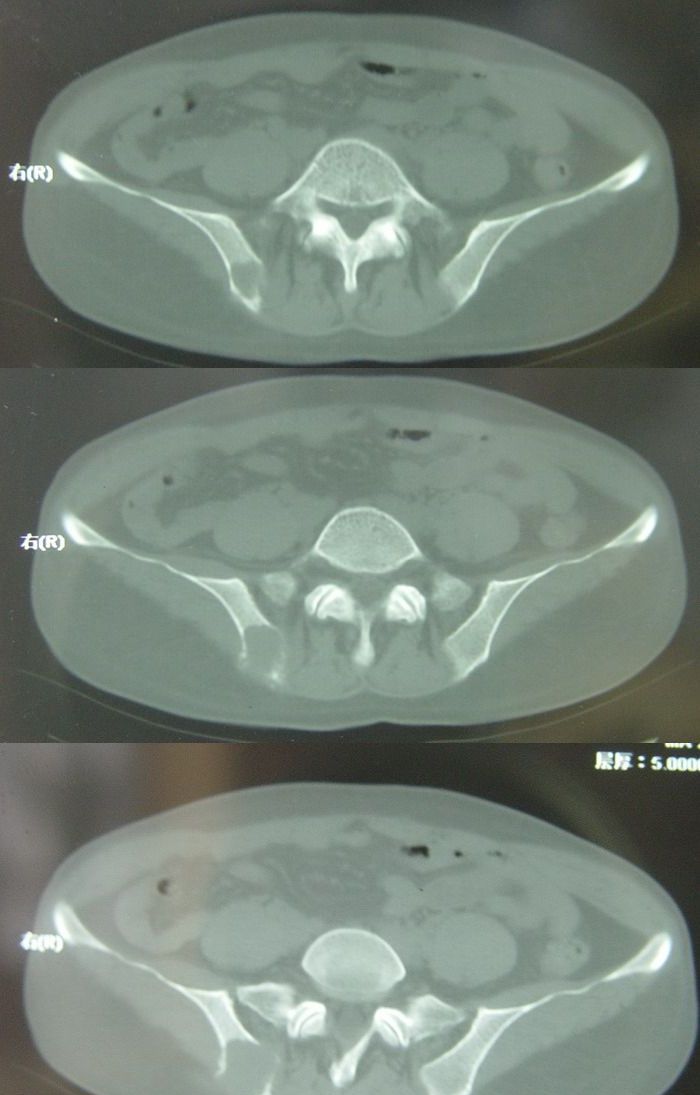

标题: CT13002:女,46岁。有子宫肌瘤手术史,现在出现右臀部向腿 [打印本页]

标题: CT13002:女,46岁。有子宫肌瘤手术史,现在出现右臀部向腿

右侧髂骨后缘囊状膨胀性骨质改变,无明显骨间隔,周围无明显硬化及骨膜反应,周围软组织无异常,相邻骨组织密度增高,考虑:动脉瘤样骨囊肿可能,要注意与骨巨细胞瘤及转移瘤鉴别。

右侧髂骨膨胀性骨质破坏区 囊内密度尚均匀 骨巨细胞瘤可能性大 动脉瘤样骨囊肿不除外 建议mr观察囊内成分明确诊断 左侧附件区包裹性积液

右侧髂后上棘局限性囊状骨质破坏,大部分界清,似见轻度硬化边,内无分格及钙化,病灶上部局部显示模糊。考虑;骨巨细胞瘤可能大,不除外abc。另可见子宫肌瘤术后子宫缺如。

临床和影像学表现:女性患者46岁,有子宫肌瘤手术病史。影像所见可见残余宫颈部分,左右附件未见新生物;右髂骨翼后端囊状膨胀性骨破坏,囊性部分感觉有强化(楼主标上增强前后的ct值就很好了),未见明确的液—液平面,周边硬化不明显或轻度硬化。

分析:患者年龄46岁,没有明确外伤病史,病变呈膨胀性骨破坏,囊性部分未见明确的液—液平面,周边硬化不明显。综合分析该病例比较符合骨巨细胞瘤,不太符合动脉瘤样骨囊肿。

诊断:1、首先考虑骨巨细胞瘤;2子宫肌瘤术后改变